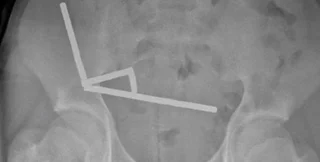

После того, как врачи сделали рентгеновские снимки брюшной полости подростка, они обнаружили, что в разных отделах кишечника мальчика находятся четыре линейных цепочки из неодимовых магнитов, которые соединились. Мелкие металлические предметы соединились, создав разрушительные последствия.

Рентгеновский снимок, на котором видны цепочки магнитов в брюшной полости новозеландского подростка

Фото: ScienceAlert

Хирурги провели операцию и обнаружили, что магниты находятся в разных отделах тонкой и слепой кишки. Соединяясь, магниты вызвали отмирание нескольких участков ткани из-за недостатка крови. Поэтому хирургам пришлось удалить часть кишечника мальчика. Несмотря на это подросток поправился и был выписан из больницы через восемь дней после операции.